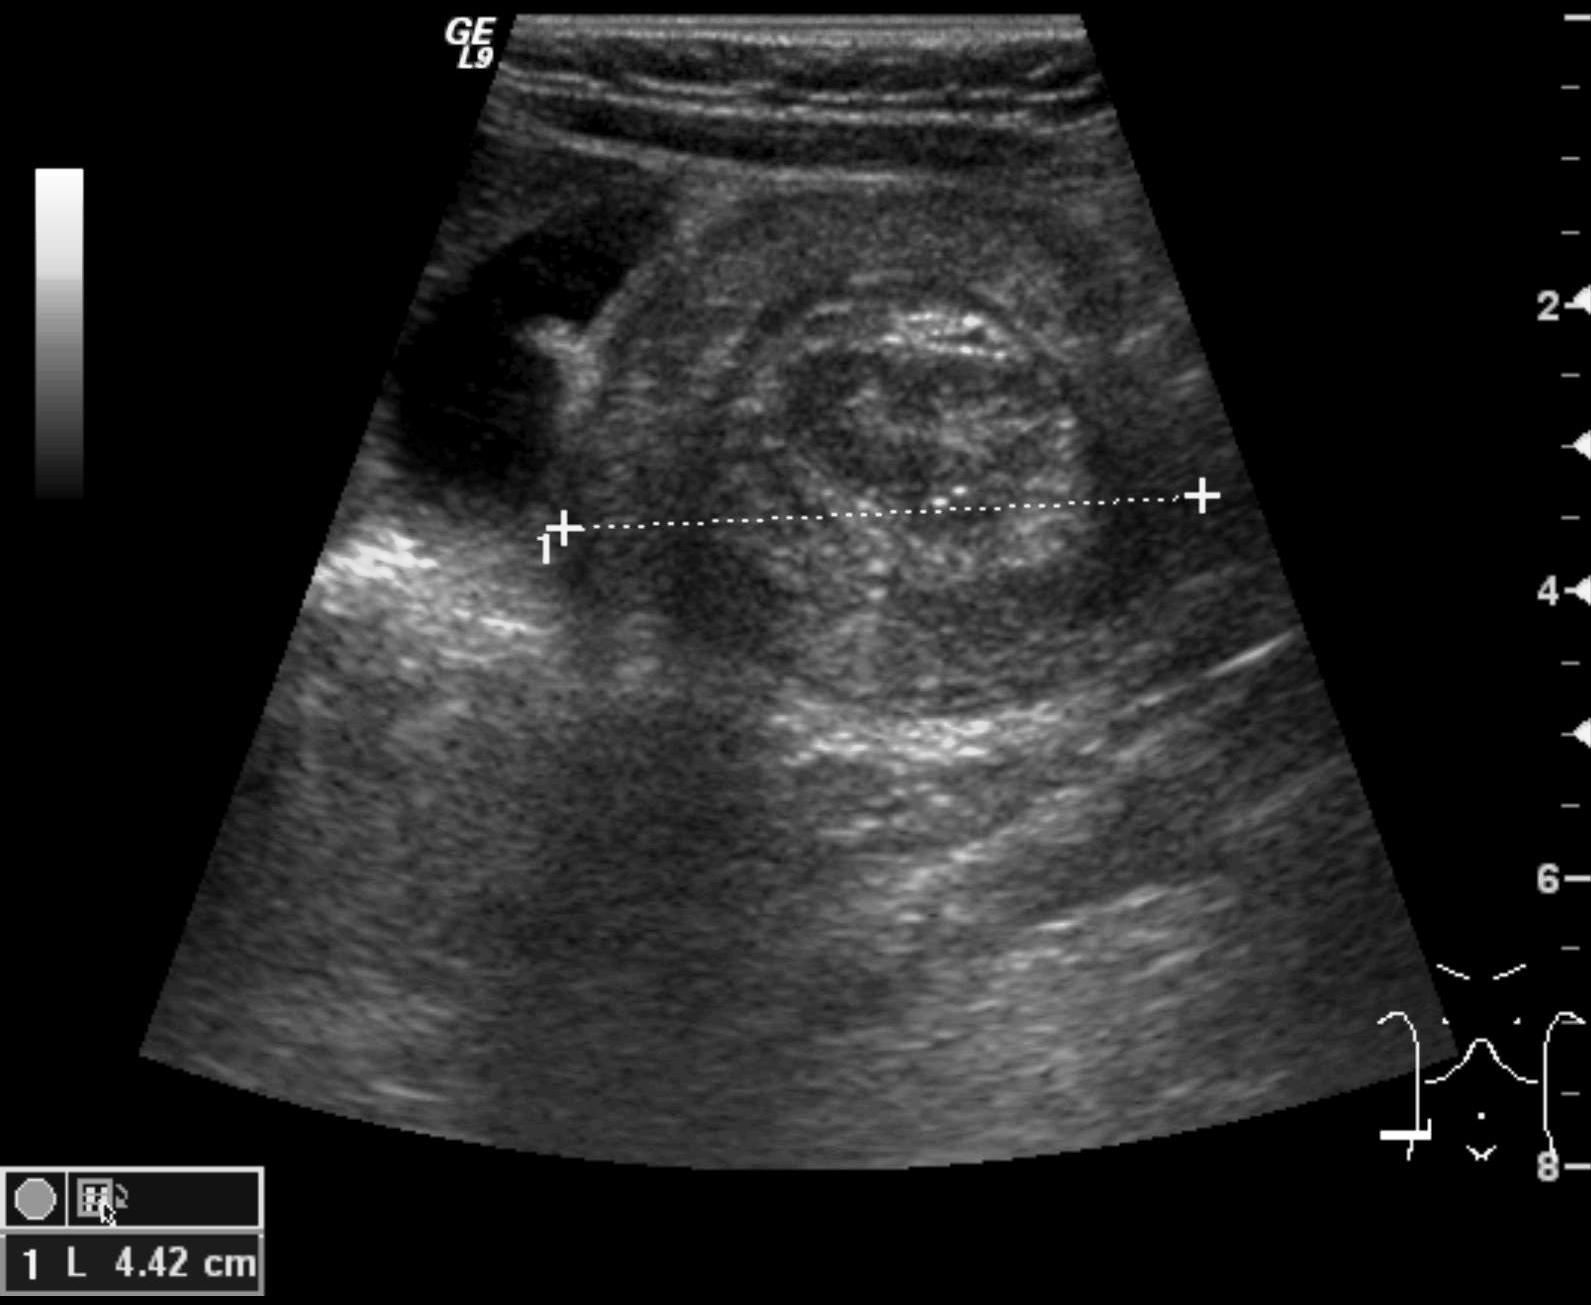

Invagination. A distal intestinal loop invaginating to a proximal intestinal loop can result in a mechanical intestinal obstruction, and cause ischemic damage. It most frequently occurs in infants (3-24 months) with recurring, colic-like complaints, distended intestines, a palpable mass and with frequent vomiting and bloody stool. Invagination requires immediate diagnosis and desinvagination. US exam reveals the invaginated intestines as a “target” sign in axial cross section and looks like a “pseudokidney” in longitudinal cross section. The therapy is hydrostatic or pneumatic desinvagination. Perforation and/or peritonitis are absolute contraindications to these procedures. Hydrostatic desinvagination can be performed under fluoroscopy or with US guidance and is considered successful if air or the contrast material appears in the terminal ileum and the invaginated loop disappears. If these efforts do not succeed, surgical desinvagination is needed.

17. “Target” sign. Invagination. .

18.a-b-c-Desinvagination with air.

18. b. Arrow: invaginated segment.

18. c. Successful desinvagination